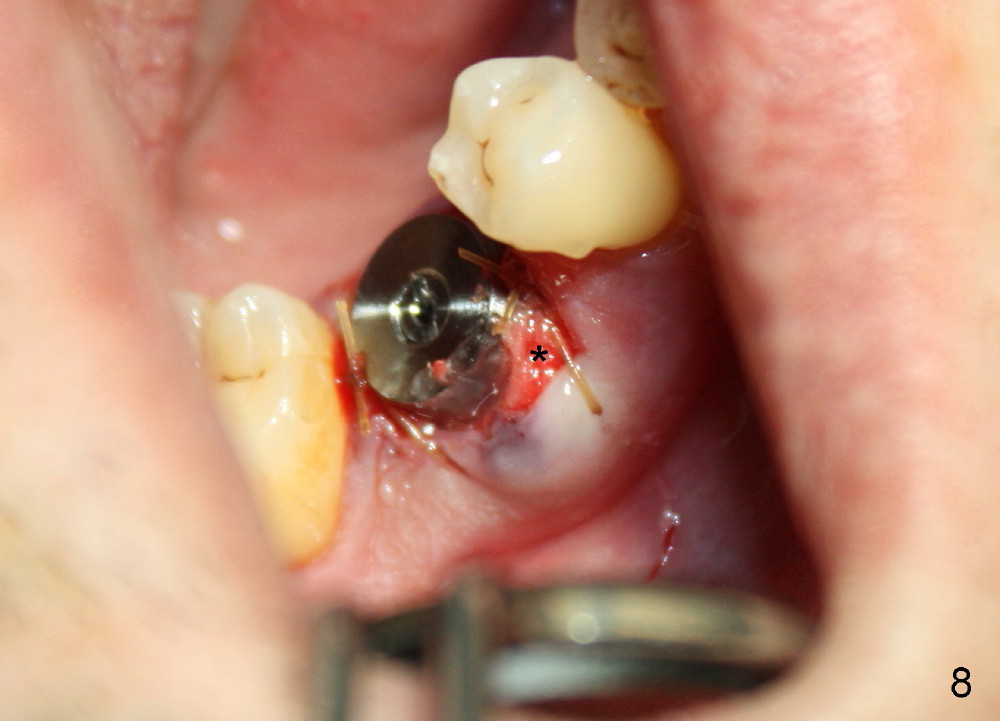

The distal socket is closed completely with suture, whereas the mesiobuccal space is partially closed with collagen gauze and suture (Fig.8 *). The wound is then covered by perio dressing. The gingiva heals around the implant 18 days postop (Fig.9). Three months postop, the implant is stable. The mesial upper portion of the threads appears to have better contact with the bone (Fig.10 <, as compared to Fig.7); the density of the distal socket seems to increase (*). There is no buccal plate atrophy (Fig.11 ^). Supragingival margin is designed for the crown to prevent periimplantitis (Fig.12)